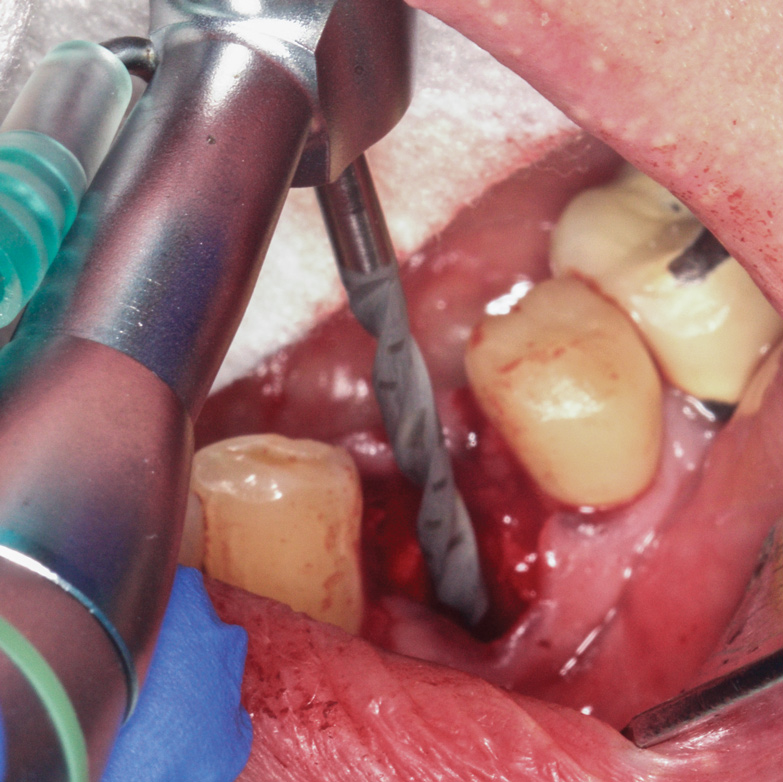

Prior to drilling the osteotomy, a landmark point on the patient scan was verified against direct visualization by placing the drill tip on the chosen anatomical landmark. Surgery proceeded under RADS guidance, in the form of auditory feedback (ie, mode-change and warning beeps) and haptic feedback (ie, resistance to drill motion) as well as visual guidance via a monitor (ie, navigation). To initiate the osteotomy, a 2.3-mm round drill was placed in the robotic guidance arm. As per the implant manufacturer's recommendations, three subsequent drills were used to perform the osteotomy in the prescribed location and angulation (Figure 4 and Figure 5). Implant placement was also achieved with the RADS system (Figure 6 and Figure 7).

Fig 4. Osteotomy into the extraction socket under robotic guidance.

Figure 4

Fig 5. Osteotomy into the extraction socket under robotic guidance.

Figure 5